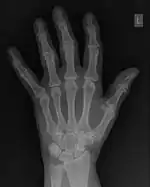

The conventional way of interpreting radiographic images in medicine is to regard them as representations of human anatomy. In the mathematical analysis of these images, however, we can interpret them as fluctuations of signal amplitude in space, as demonstrated in Figure 1.23.

FFTs can also be calculated in two-dimensions to give results such as those in Figure 1.27. Since Fourier analysis generates results in terms of both positive and negative spatial frequencies, these can be plotted in the form of a 2D image so that the maximum frequency lies at the origin and those for the horizontal and vertical directions are shown increasing towards that origin. The modulation at different spatial frequencies is represented using a grey-scale. Low frequency bands can be seen along the horizontal axis in the figure, for example, representing the horizontal periodicity of image data from the fingers, while finer bands along the y-dimension are indicative of a periodicity of image data from the various metacarpophalangeal joints. Higher frequency features can also be seen running diagonally in this 2D-FFT, representative of the trabecular structure of the bones, for example.